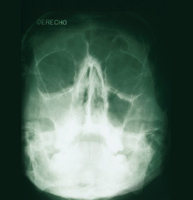

El diagnóstico de la sinusitis aguda se basa en una exploración física y la explicación por parte del paciente de los síntomas. Puede ser necesaria una radiografía y una muestra de la mucosidad para analizar la bacteria. Si se padece de sinusitis con frecuencia o cuando la infección dura tres meses o más, puede tratarse de una sinusitis crónica. Los síntomas de una sinusitis crónica pueden ser menos severos que los de una sinusitis aguda. La sinusitis crónica puede producir cambios irreversibles que requieren el uso de la cirugía para repararlos. La alergia por hongos también pueden causar sinusitis, y sus síntomas se asemejan más a los de una sinusitis crónica que a los de una sinusitis aguda.

- Cirugía de Senos. Sólo si la medicación falla o la obstrucción nasal no se puede corregir con medicamentos, se puede considerar la cirugía. La cirugía endoscópica se recomienda para ciertos tipos de desórdenes sinusales. El endoscopio permite al cirujano ver directamente el interior de la nariz, y al mismo tiempo, eliminar tejidos y pólipos y limpiar los canales estrechos que hay entre los senos. La decisión de usar anestesia local o general se hará siempre de acuerdo con el paciente, dependiendo de sus circunstancias personales. Antes de la cirugía, usted ha de estar seguro que tiene expectativas realistas sobre los resultados, la recuperación y las curas postoperatorias. Los mejores resultados se obtienen, no sólo por el uso de técnicas sofisticadas, sino por el esfuerzo y la cooperación entre el paciente y el médico. Es igualmente importante que el paciente siga exactamente las instrucciones que le dé su médico antes y después de la intervención.